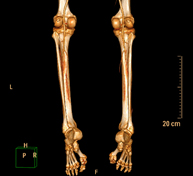

- TC d'ossos llargs Exploració radiològica que mitjançant un sistema de raigs X i detectors que giren al voltant del pacient i que reconstrueixen les imatges per ordinador (TC Multidetector), permet l'estudi detallat dels ossos llargs (tíbia, peroné, fèmur, húmer, radi i cúbit). Exploració radiològica que mitjançant un sistema de raigs X i detectors que giren al voltant del pacient i que reconstrueixen les imatges per ordinador (TC Multidetector), permet l'estudi detallat dels ossos llargs (tíbia, peroné, fèmur, húmer, radi i cúbit).